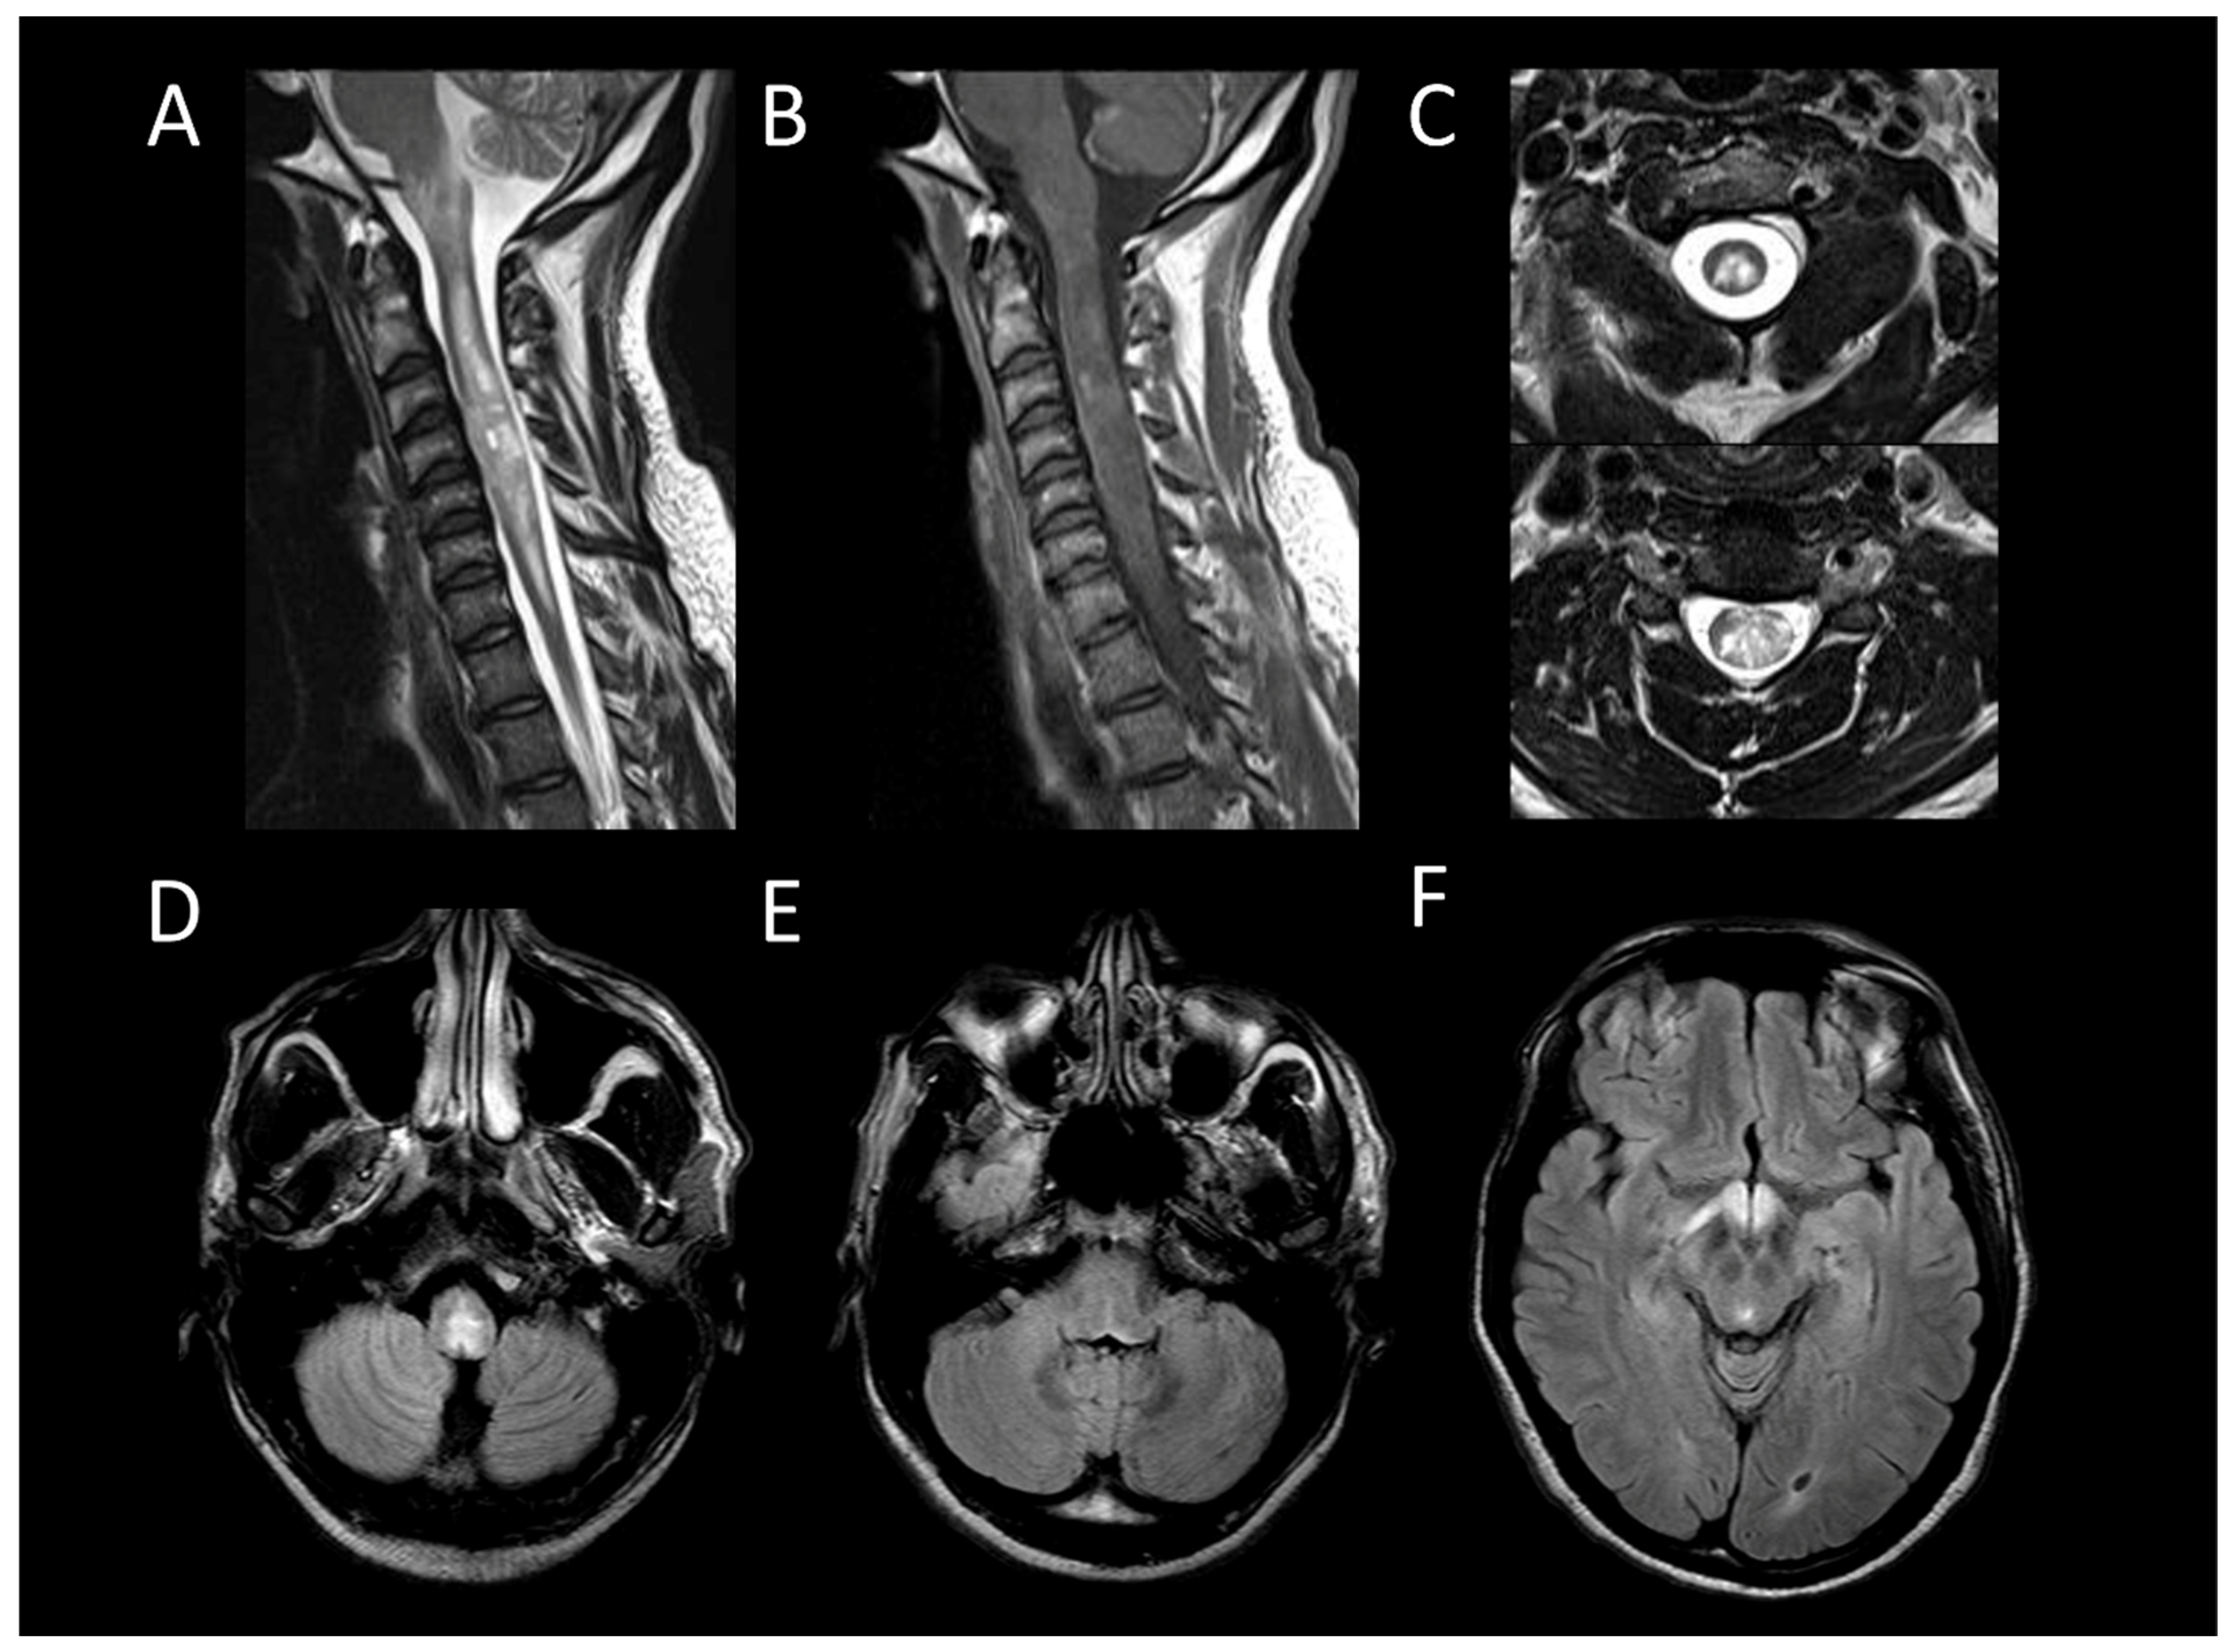

Multiple Sclerosis

Neuromyelitis Optica Spectrum Disorders Positive for Aquaporin-4 IgG

Myelin-Oligodendrocyte Glycoprotein Antibody Associated Disease

Neurosarcoidosis

Anti-GFAP Encephalomyelitis